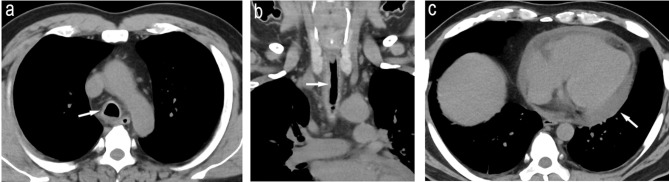

A 51-year-old Japanese man was diagnosed with left-sided ulcerative colitis (UC) at age 41. He was treated with mesalazine and azathioprine and maintained remission. At age 51, the patient developed bloody stools, abdominal pain, scleritis, arthritis, cough, bloody sputum, and pericardial effusion. Considering that pericardial effusion is an atypical extraintestinal complication of UC, and the patient met the diagnostic criteria for relapsing polychondritis (RP), a diagnosis of RP complicating a relapse of UC was made. Steroid therapy was administered, and both diseases improved. Golimumab, an anti-tumor necrosis factor-α inhibitor, was introduced as maintenance therapy for UC. All symptoms, including pericardial effusion, improved. Subsequently, no relapse of UC or RP was observed. As only a few cases of RP overlapping with UC have been reported and no treatment protocol has been established, we considered this case valuable and worthy of publication.